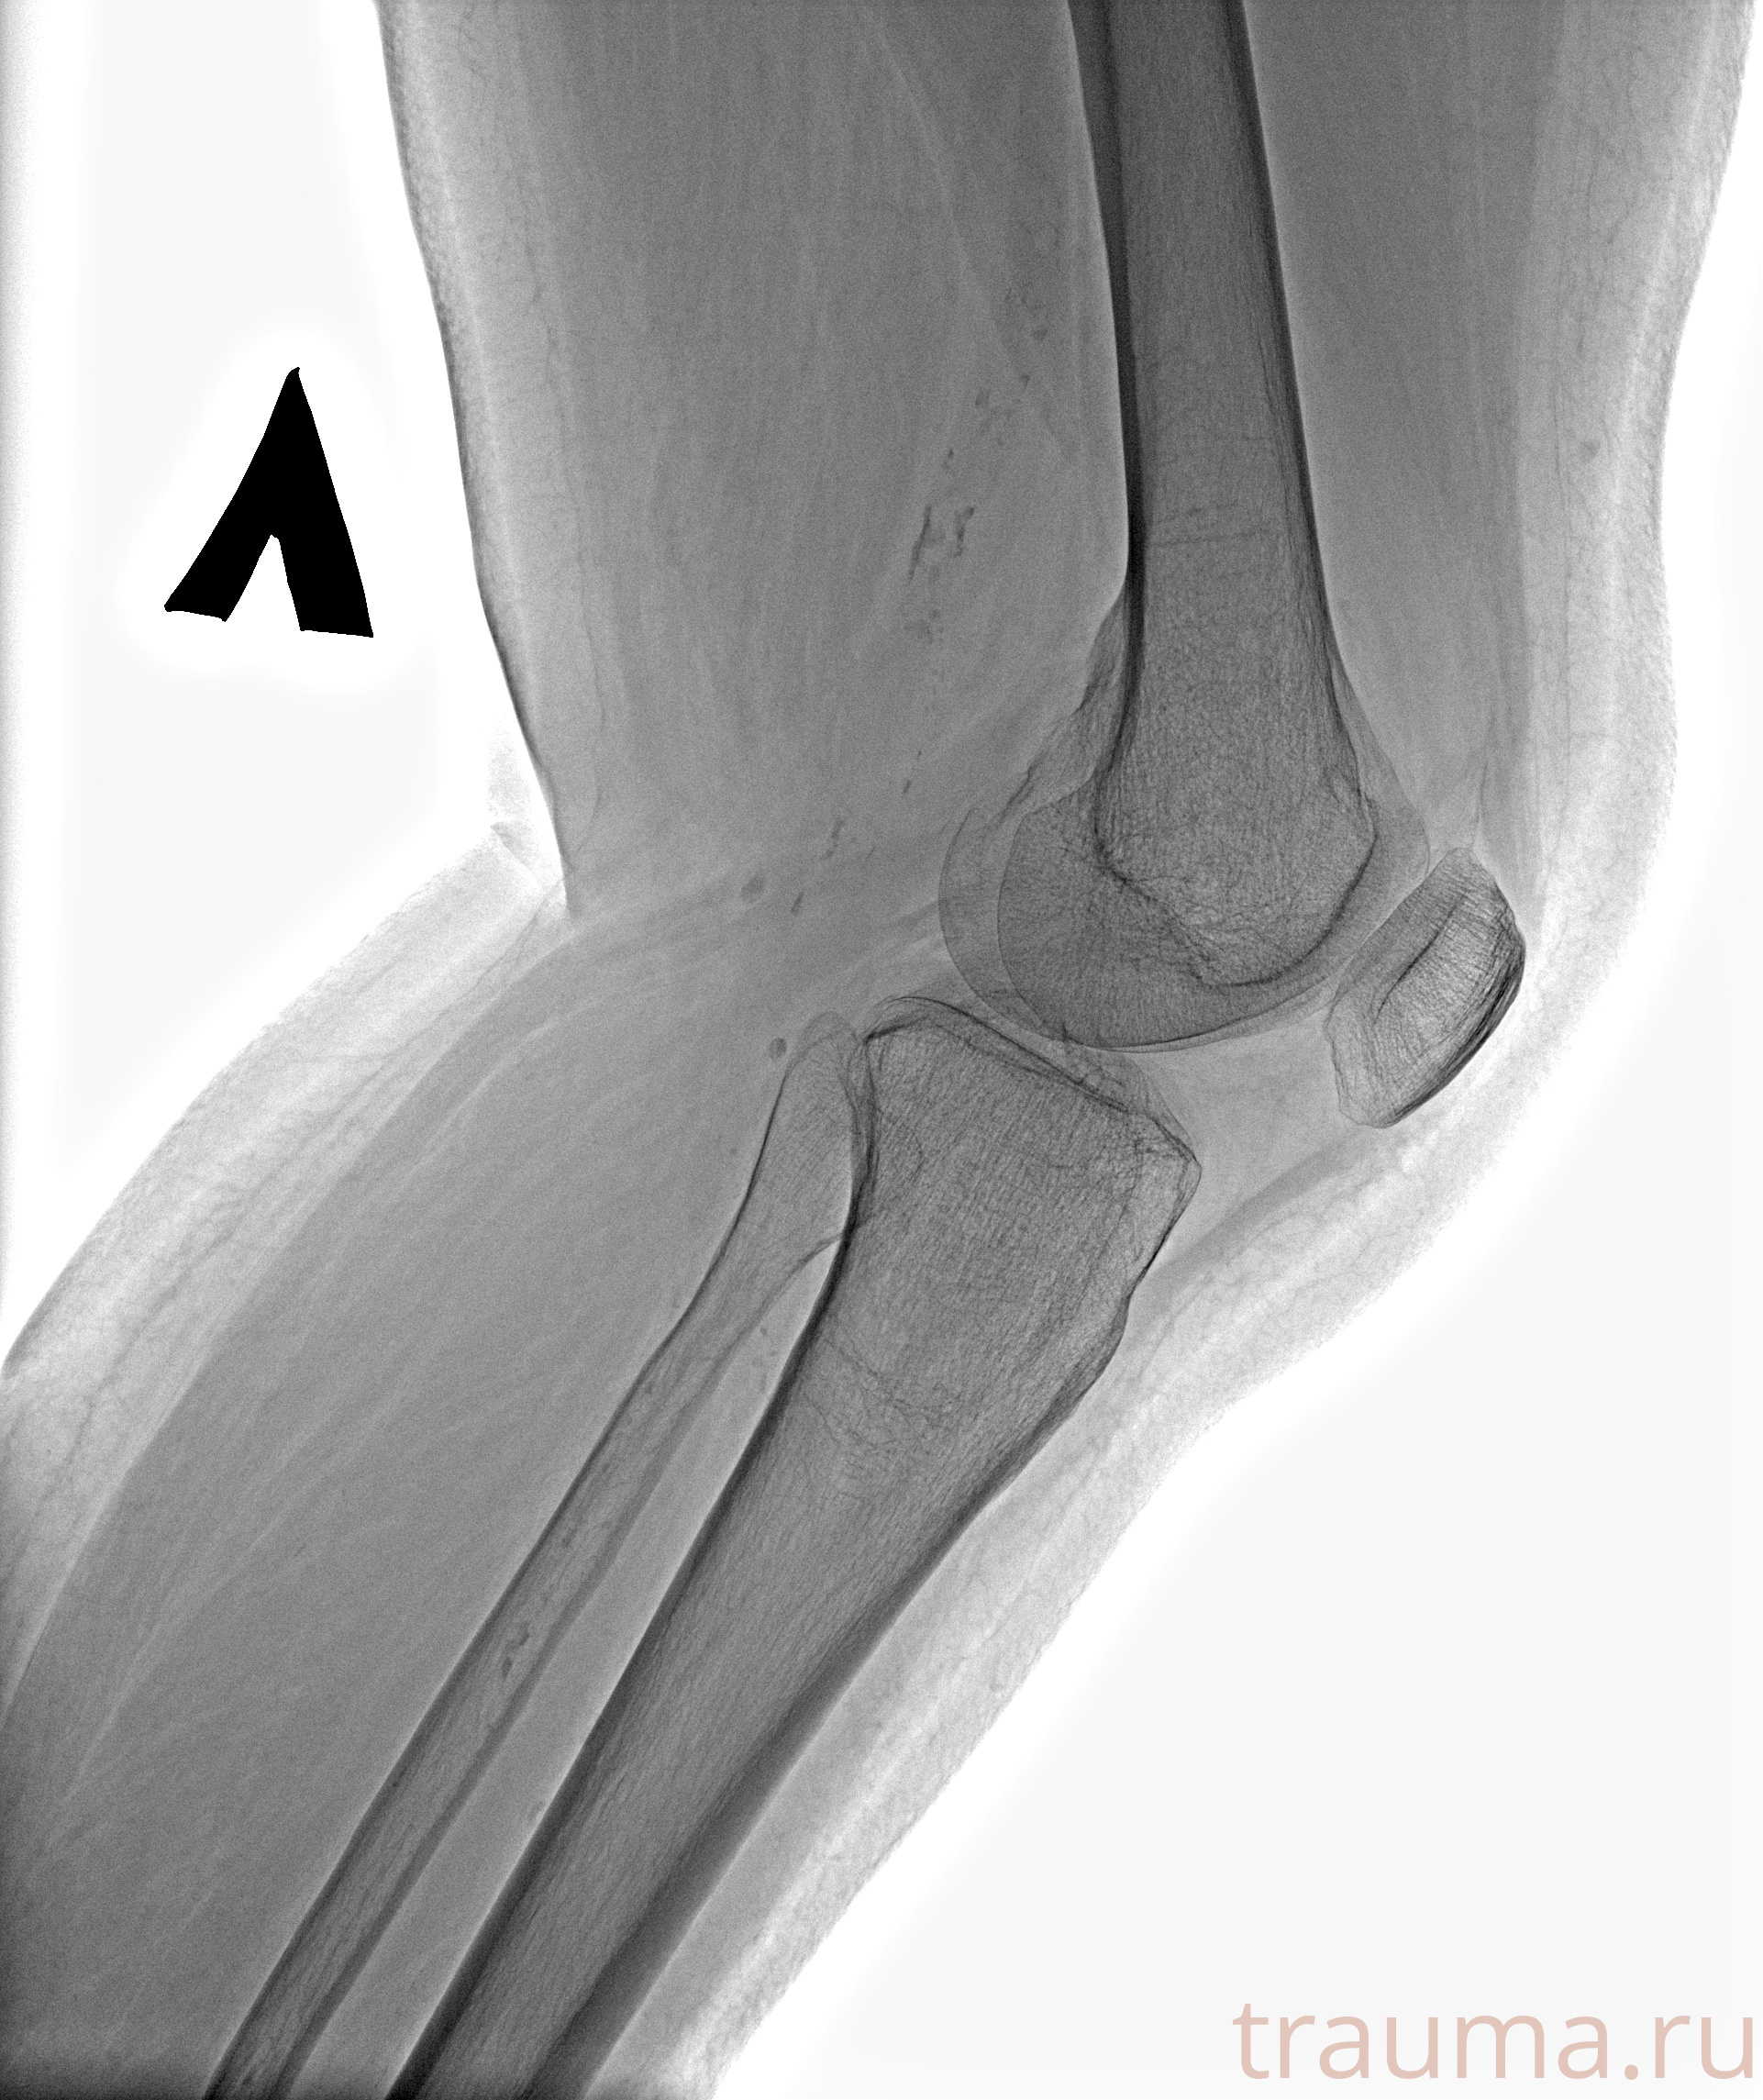

Рентгенограммы

Рентген на дому: по вашему адресу приезжает врач-рентгенолог, травматолог-ортопед с мобильным рентгеновским аппаратом, проводит диагностику травмы или заболевания, делает необходимые рентгенограммы, дает рекомендации по дальнейшему лечению. Получить качественные снимки в домашних условиях возможно благодаря уникальной методике, разработанной МосРентген Центром для института  Склифосовского